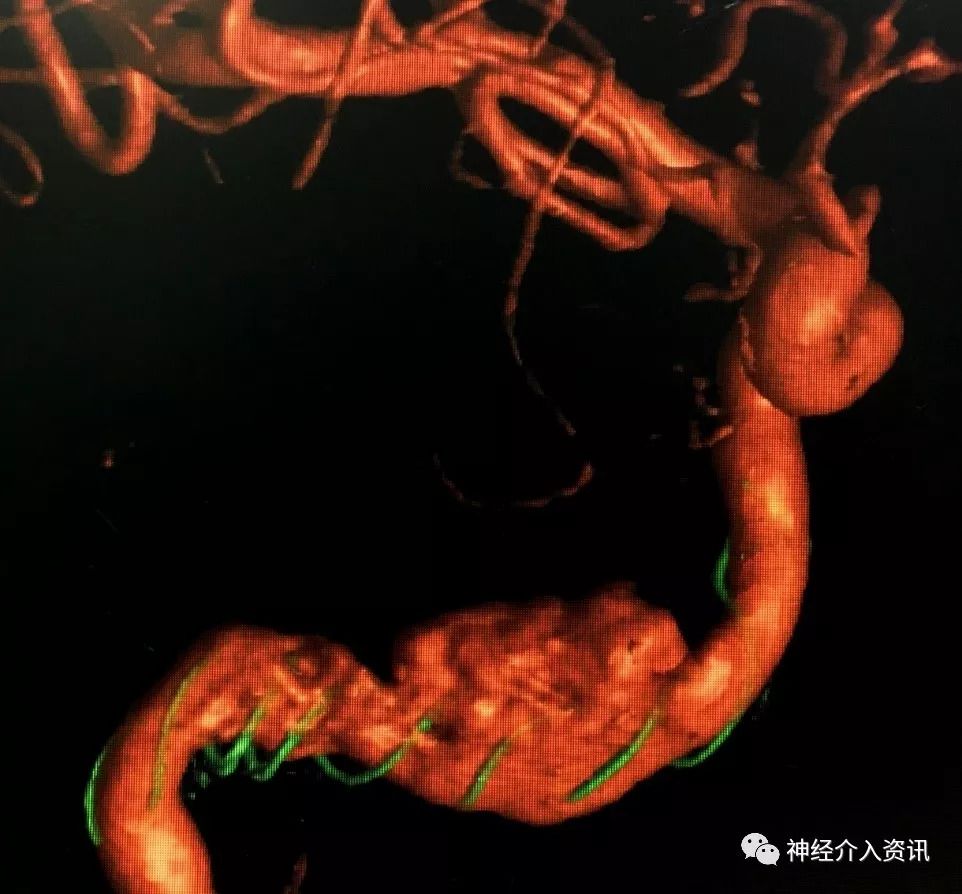

该患者因右眼外展受限引发复视,行DSA检查发现右侧颈内动脉岩骨段长节段夹层动脉瘤(图1)。夹层主体长径约18.3mm,其近端还有约5mm梭形扩张。传统的夹层动脉瘤治疗方法为支架辅助弹簧圈栓塞,需要多枚弹簧圈,同时多枚支架桥接覆盖夹层段对受累血管进行覆盖,且术后伴有较高的复发率。由于术中需要置入多根微导管,操作复杂;介入耗材使用多,花费高;局部占位效应明显,术后对外展神经压迫较持久,症状改善缓慢或是效果不满意;普通支架金属覆盖率低,术后复发率较高。结合病人动脉瘤的特点及临床表现,经过科室反复讨论,王东海教授治疗团队提出新思路并与家属沟通后,拟实施血管重建装置的血管内治疗。血管重建装置(Tubridge®)是由上海长海医院刘建民教授主导研发的有自主知识产权的国产支架,经过近6年的临床预试验后,被证实安全有效并于今年在国内上市。其特点是在血管内较高的金属覆盖率,良好的血管导向性,精准的尺寸适应不同条件的血管,低花费,低复发率使其在临床上具有广泛使用的空间。

图1:颅脑DSA检查提示右侧颈内动脉夹层动脉瘤,近端及远端夹层共累及血管长度约22mm。